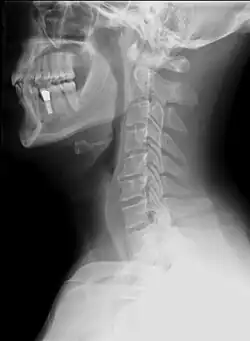

- Une radiographie du rachis cervical de face et de profil et en fonction de la localisation un autre cliché cette fois de face et la bouche ouverte pour voir les deux premières vertèbres cervicales ;